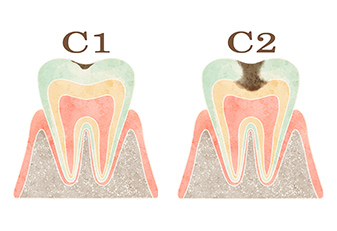

当院では、歯を残すことを第一に考え、むし歯に感染した必要最小限の箇所だけを削り取り、

患者さんの大切な歯をできるだけ残せるよう治療いたします。

むし歯の部分を取り除ぎます。

むし歯を取り除いた部分には小さな穴ができるので、細菌が入り込まないように「コンポジットレジン」といわれる歯の色に似た詰め物で塞ぎます。

歯の内部に入った細菌を除去し、痛みや腫れを取り除く治療を行います。取り除いた部分には、歯型を取って作製した修復物を被せます。被せ物を安定させるために、歯の土台(コア)が必要になることがあります。

C4は歯の頭の大部分がむし歯により失われた状態です。場合によっては抜歯になることがあります。